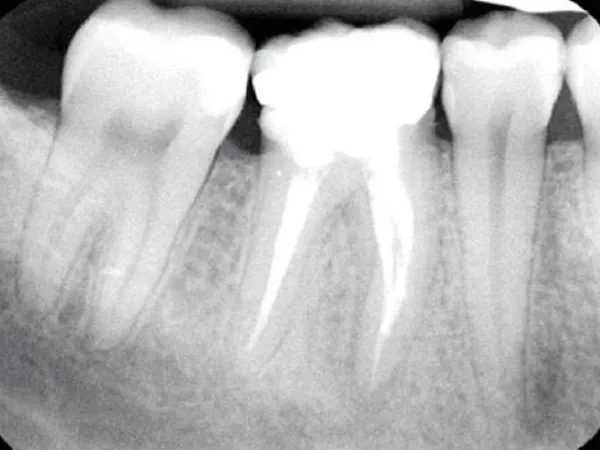

درمان ریشه یا اندودانتیکس یکی از حساسترین و تخصصیترین خدمات دندانپزشکی است که در کلینیک نیکا توسط متخصصین مجرب و با استفاده از تجهیزات دیجیتال پیشرفته انجام میشود. این درمان زمانی انجام میشود که پالپ دندان (بافت نرم داخل ریشه) دچار التهاب یا عفونت شده باشد. در کلینیک نیکا، مراحل درمان شامل تصویربرداری دقیق با دستگاههای دیجیتال، بیحسی موضعی بدون درد، پاکسازی کامل کانالهای ریشه و پرکردن آنها با مواد زیستسازگار است. استفاده از لوپهای بزرگنمایی و فایلهای روتاری باعث افزایش دقت و کاهش احتمال شکست درمان میشود

در این فرآیند، دندانپزشک با استفاده از ابزارهای تخصصی، پالپ آلوده را خارج کرده Pulpectomy، کانالهای ریشه را پاکسازی و ضدعفونی میکند Canal Disinfection، سپس آنها را با مواد پرکننده مخصوص مانند گوتاپرکا (Gutta-Percha) مهر و موم مینماید. در بسیاری موارد، برای افزایش دوام و عملکرد، از روکش دندان Dental Crown استفاده میشود.